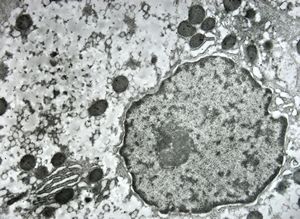

M,19y. | normal hepatocyte